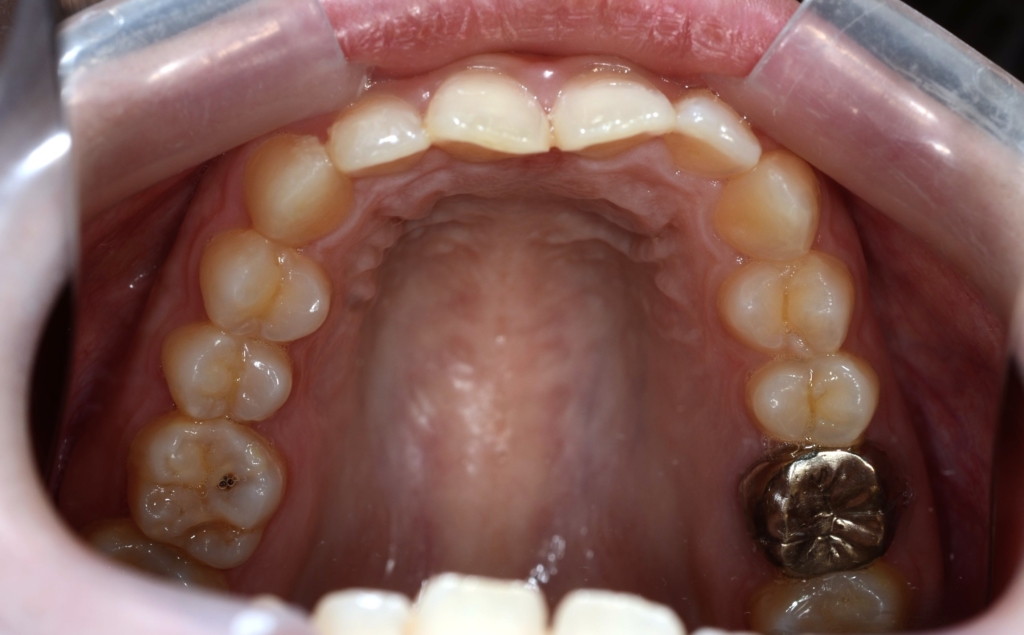

【Before】

レントゲン写真を確認すると、

【診断】

#1.上顎前突

#2.ガミースマイル(重度の過蓋咬合を伴う)

と診断しました。

【抜歯】

上の左右の奥歯を1本ずつ計2本抜歯(前から4番目の第一小臼歯です)

下は非抜歯です